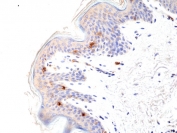

CD1A Antibody for IHC. Immunohistochemistry analysis of CD1A / CD1a expression in FFPE human skin tissue using CD1A Antibody. Membranous and cytoplasmic staining is observed in scattered dendritic cells within the epidermis, consistent with Langerhans cell localization, while surrounding keratinocytes remain largely negative. The distribution of CD1a-positive cells along the epithelial layer highlights tissue-resident immune surveillance at the skin barrier and supports evaluation of antigen-presenting cell presence in epithelial tissues.

Langerhans cells are dendritic cells located within the epidermis and mucosal epithelia, where they function as sentinels of the immune system by capturing, processing, and presenting antigens to T cells. CD1a expression is a defining feature of these cells, allowing them to be distinguished from surrounding epithelial cells such as keratinocytes. Detection of CD1a therefore provides a direct method for identifying immune surveillance cells within epithelial layers and assessing their spatial distribution.

In tissue-based analyses, CD1a-positive cells are observed as scattered dendritic cells within the epithelial layer, forming a network that monitors environmental exposure and contributes to host defense. This distribution is particularly evident in skin, where Langerhans cells are positioned to detect external antigens. A CD1a antibody enables visualization of these cells within intact tissue architecture, supporting evaluation of immune surveillance activity in epithelial environments.